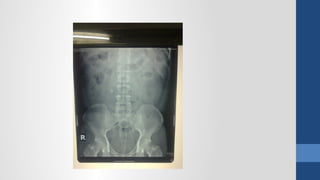

2. Ch n đoán hình nhẩ ả

Xquang b ng đ ng không chu n bụ ứ ẩ ị

2. Ch nđoán hình nhẩ ả Siêu âm Xquang b ng đ ng không chu n bụ ứ ẩ ị CT Scanner N i soi thăm dòộ

• #64 Xquang - Viêm phổi (thâm nhiễm phổi), - Tắc ruột (mức nước hơi), - Thủng tạng rỗng (hơi tự do trong bụng), - Sỏi thận và hệ niệu (vôi hóa bất thường), - Viêm RT (fecalith)?, - Thoát vị kẹt (ruột trồi khỏi giới hạn ổ bụng)?, - Nhồi máu mạc treo (hơi trong TM cửa), - Viêm tụy mãn (vôi hóa tụy), - Viêm tụy cấp (sentinel loop, colon cutoff), - Phình ĐM (bờ vôi hóa)?, - Tụ máu hoặc áp xe sau phúc mạc (mất bóng cơ psoas), Siêu âm - Những bệnh vùng chậu (u buồng trứng, Viêm RT cấp, thai ngoài tử cung, thai trong tử cung), - Sỏi mật (túi mật, đường mật), - Gan (áp xe, bướu gan), - Thận (ứ nước, sỏi), - Dịch tự do trong bụng (xuất huyết nội, dịch viêm, ascites) CT Scan: - có giá trị định bệnh cao hơn SA nhưng không nên dùng cho BN nữ đang mang thai hoặc cho trẻ em. - Viêm đại tràng thiếu máu (dấu ấn ngón tay trên thành đại tràng). &amp;lt;number&amp;gt;

• #67 Ngoài ra trên xquang đến với chúng ta còn thấy được j nữa. Bóng thận lớn? Bn trên siêu âm (9cm) bn trên xquang (3 đốt sống) &amp;lt;number&amp;gt;